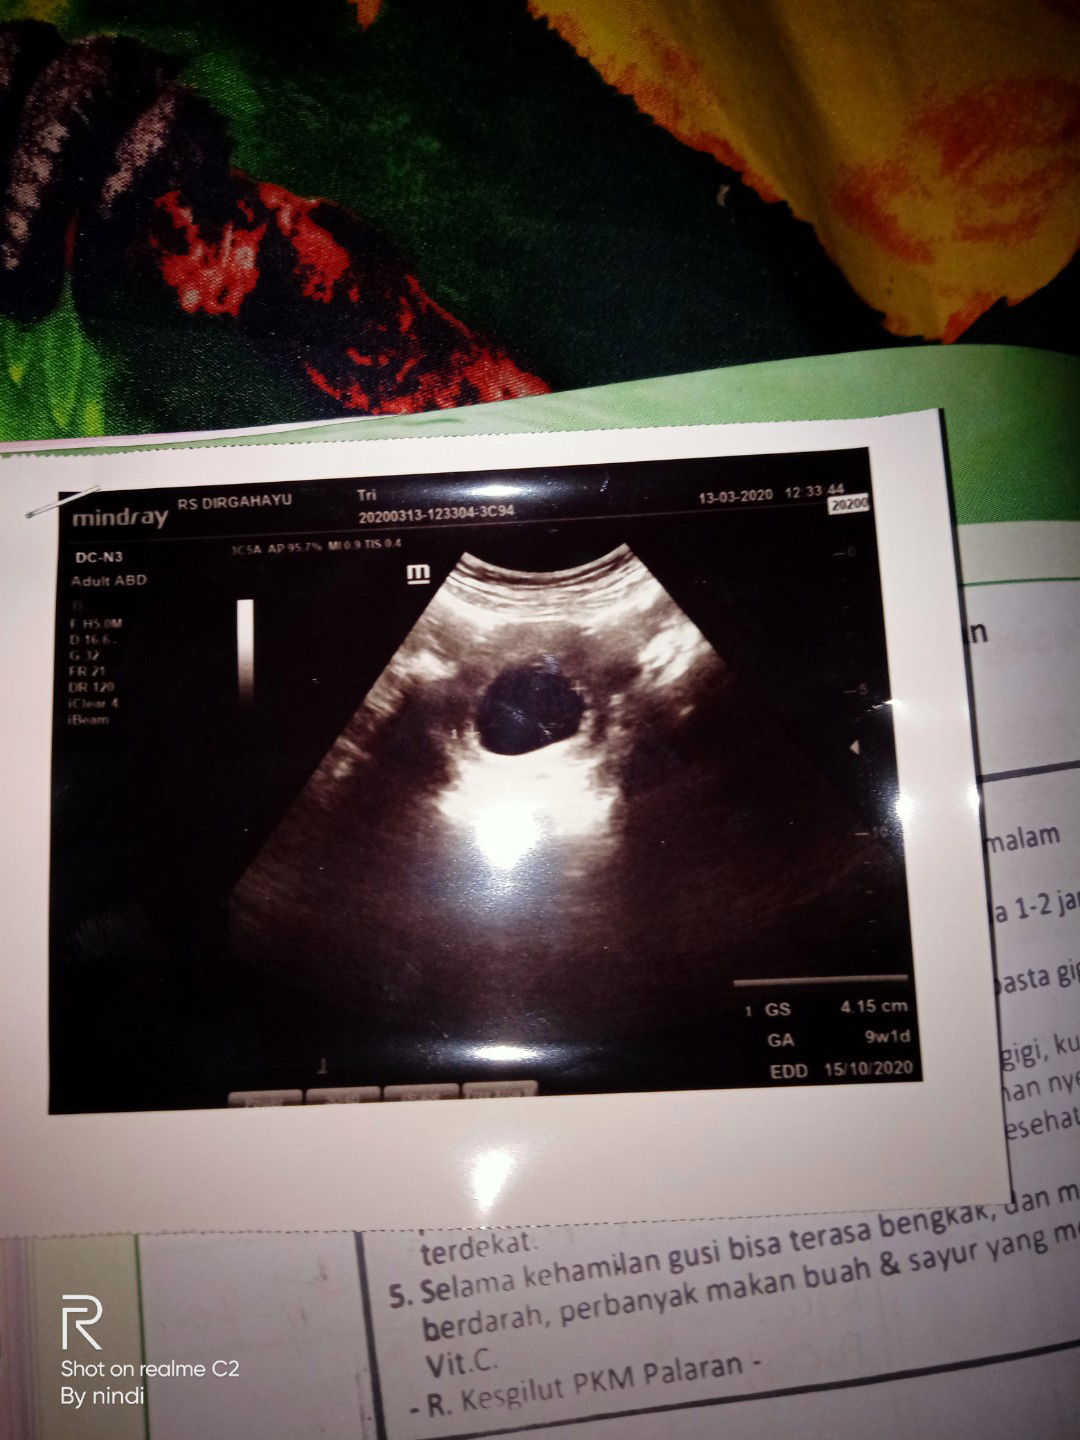

Assalamualaikum Bun ada yg pernah ngalamin hamil tapi janin tidak berkembang. Tgl 13 bln 3 aku pendarahan Bun tapi ngeflek aja Bun trus aku periksa kan ke dokter obg ,,sama dokternya di USG pas di USG hanya kelihatan kantong kehamilan aja Bun janin tidak ada,,bilang nya dokter janin tidak berkembang.. dokter nyaranin harus di kuret ,tapi saya masih ingin mempertahankan trus sama dokternya di kasih penguat kandungan ,,dan bilang nya disuruh kembali lagi tanggal 19,kalau tanggal 19 periksa di USG ada perkembangan janin bisa di pertahankan kalau Ndak ada harus di kuret, dan tgl 14 saya pendarahan hebat Bun langsung di bawa ke RS..dan langsung di kuret Bun..sedih rasanya Bun. Apa kah kalau hamil lagi nanti bisa terulang LG ya Bun..